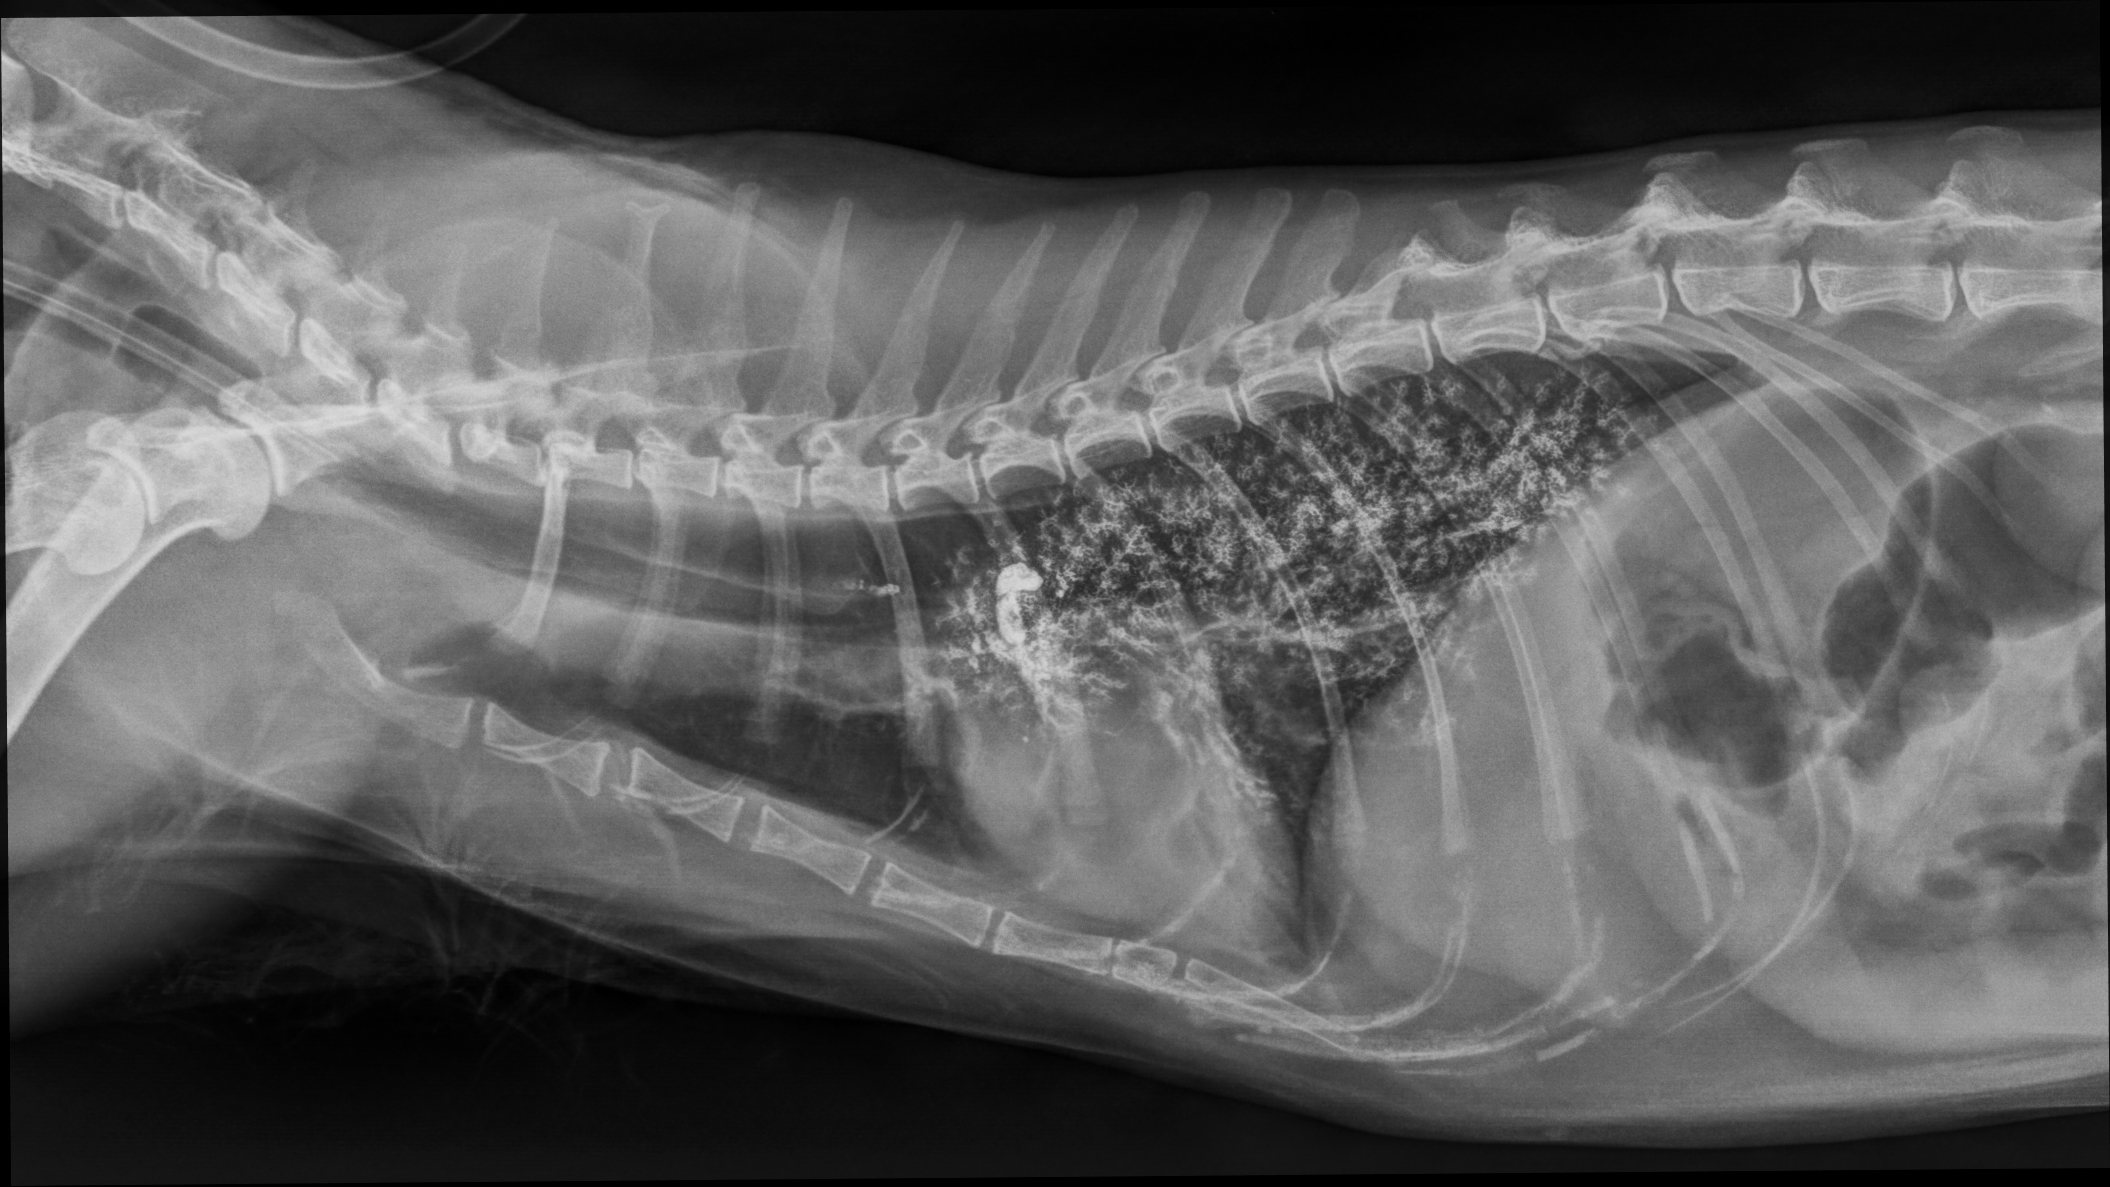

Am 10.- und 11.01.2026 ist alles Grau -in -Grau beim Röntgenkurs Thorax und Abdomen. Hier lernt garantiert jeder was dazu!